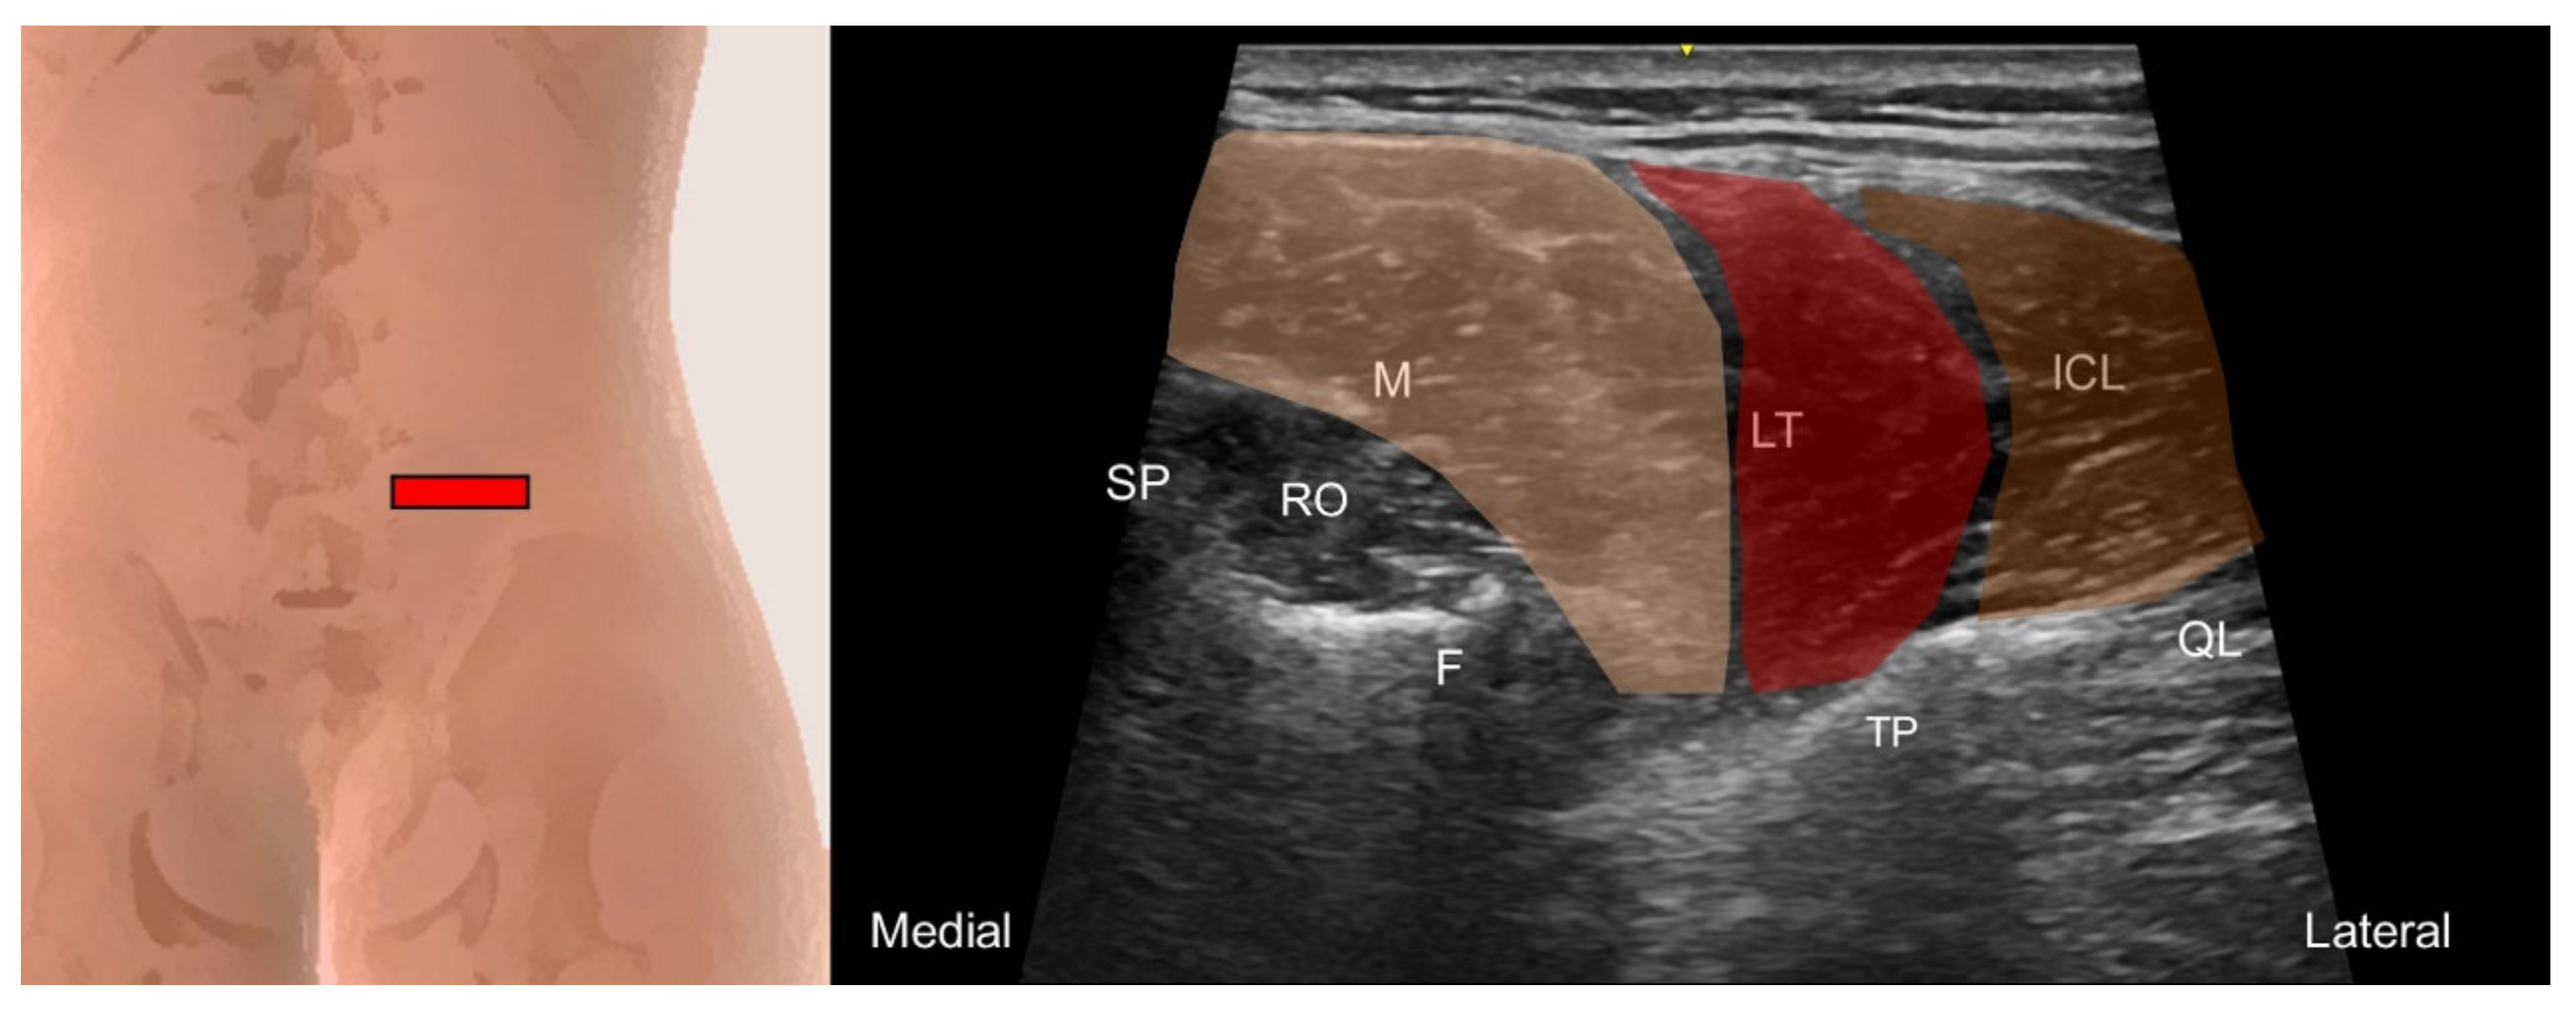

5.2. Iliocostalis Lumborum, Longissimus Thoracis, and Lumbar Multifidus

5.2.1. Anatomy

5.2.2. Sonographic Scanning

5.2.3. Clinical Relevance